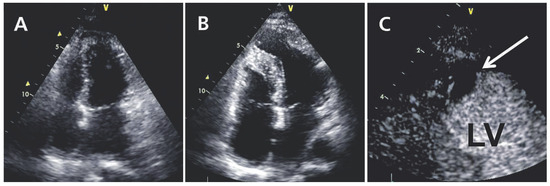

Left Ventricular Apical Thrombus Many Months After Pericardial Biopsy

by Niklas F. Ehl, Franziska Rohner, Hans Rickli and Micha T. Maeder

Cardiovasc. Med. 2013, 16(4), 132; https://doi.org/10.4414/cvm.2013.00123 - 17 Apr 2013

A 39-year-old woman presented with recurrent episodes of acute pericarditis over a four year period [...] Full article

Figure 1